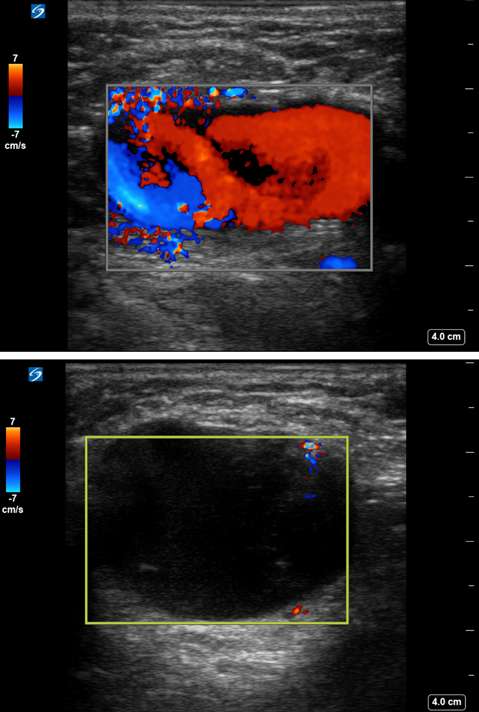

Figure 5D. Pseudoaneurysm. Immediately following endovascular intervention, ultrasound-guided thrombin injection of the pseudoaneurysm sac was performed. Pre-treatment Doppler ultrasonography (top) demonstrates persistent filling of the pseudoaneurysm sac. Post-treatment Doppler ultrasonography (bottom) demonstrates cessation of internal flow, compatible with complete thrombosis and treatment success.